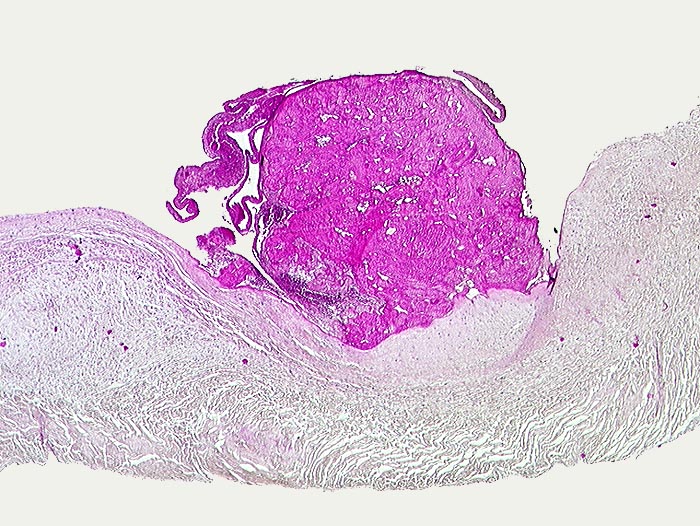

PathoPic ID 113 - Endocarditis marantica

Endocarditis marantica

Entzündung / Reparatur

Aortenklappe

Kardiovaskuläres System

Knotenförmige Fibrinauflagerungen auf dem Klappengerüst.

Metastasierendes Bronchuskarzinom.

Histologie